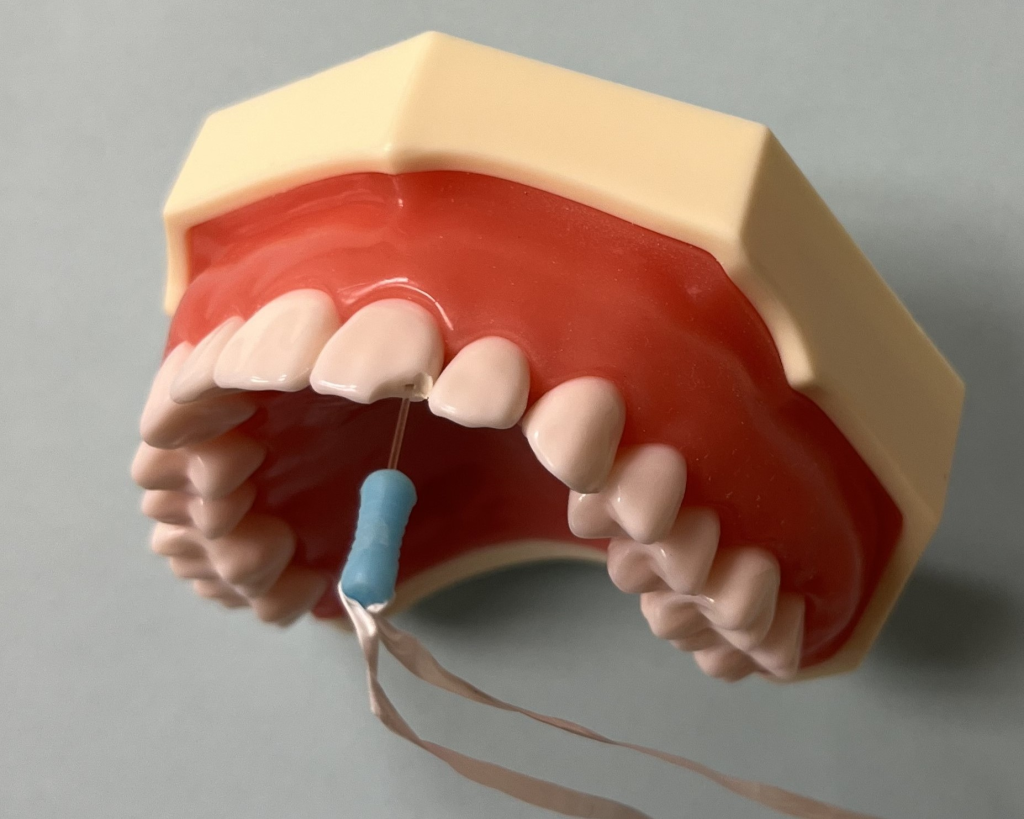

Add Floss to Pin

Be sure to attach floss to the handle of the pin to ensure it is not swallowed or aspirated during the procedure. See the picture above.

Inserting Pin

Using the custom bur provided in the kit, drill the hole to the desired depth and rinse. Using any bonding system, coat the hole, tooth, and glass pin with bonding agent. Place a drop of flowable composite on the tip of the DentXpinTM. Insert the pin into the hole while wet, then cure both the pin and the tooth.